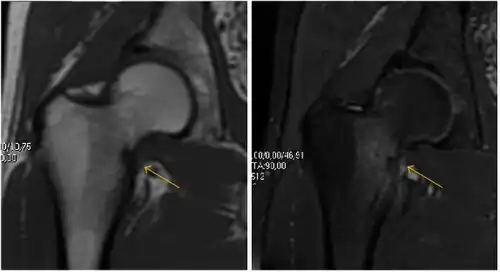

MRI has been shown to have 100% sensitivity and specificity in prospective studies of occult hip fractures. These fractures were diagnosed by bone marrow edema and a low signal fracture line, mainly on T1 or T2 weighted images (Figure 10).[1]

Figure 10:

Stress femoral neck fracture in a young athlete barely visible in X-ray film as a sclerotic line (arrow)[1]

In this case, Tc 99 scintigraphy shows a band of uptake[1]

Furthermore, T1 (left) and DP fat saturated (right) weighted MR images showed the fracture line and a pattern of edema.[1]

Nuclear Medicine

Bone scanning in people with hip pain can be complementary to other imaging studies, mainly in indeterminate bone lesions to clarify whether it is an active lesion with abnormal radiotracer accumulation. Nevertheless, MRI has replaced scintigraphy in the diagnosis of most of these conditions. An example is stress or insufficiency fractures: increased uptake is usually present in around 80% of fractures within 24 h, and 95% of fractures reveal activity by 72 h following trauma, showing an overall sensitivity of 93% and specificity of 95%. MRI is superior to bone scans in terms of sensitivity (99%-100%) and specificity (100%). Moreover, a bone scan does not provide detailed anatomical location of the fracture, and further imaging is usually required.[1]